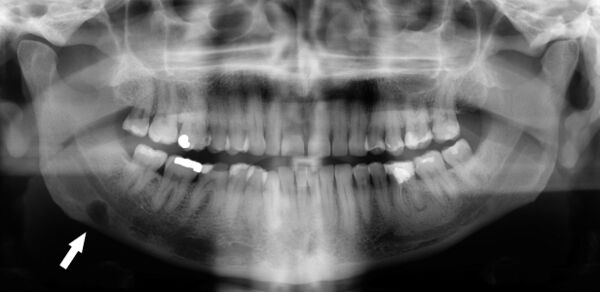

Ортопантомография (от греч.: orthos — прямой, правильный, pan — всё, tomos — ломоть, отрезанный кусок и grapho — писать, рисовать) — особый вид рентгеновской съёмки костей лицевого скелета, при котором они «развёртываются» в одну плоскость[1]. Другими словами рентгенологическое исследование в стоматологии, челюстно-лицевой хирургии, косметологии, позволяющее получать развёрнутое изображение всех зубов с челюстями, прилежащими отделами лицевого скелета. Является первичным рентгенологическим исследованием[2].

3. Костей челюстей и прилежащего лицевого скелета. Переломы (травматические, патологические) костей челюсти и лицевого скелета, новообразования, воспалительные процессы (остеомиелит, периостит), состояние полостей в костях (околоносовых пазух) и пр.

Галерея